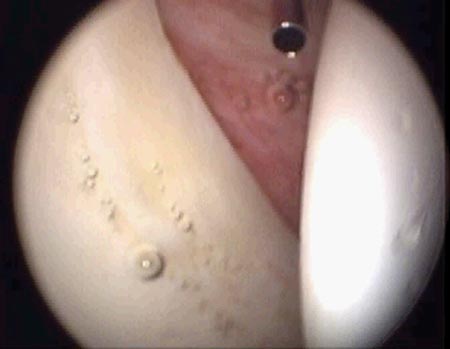

Se utilizaron para la reinserción, arpones biodegradables con sutura simple de alta resistencia. Se colocaron entre uno y tres arpones según la extensión de la lesión.

No se usaron nudos corredizos, debida a la profundidad en la localización de la cadera, y el pasaje de la sutura se hizo por la base de la lesión (Fig. 11 y 12).28,29

Figura 11: Pasaje de la sutura por la base de la lesión./ Figura 12: Reparación estable del labrum.